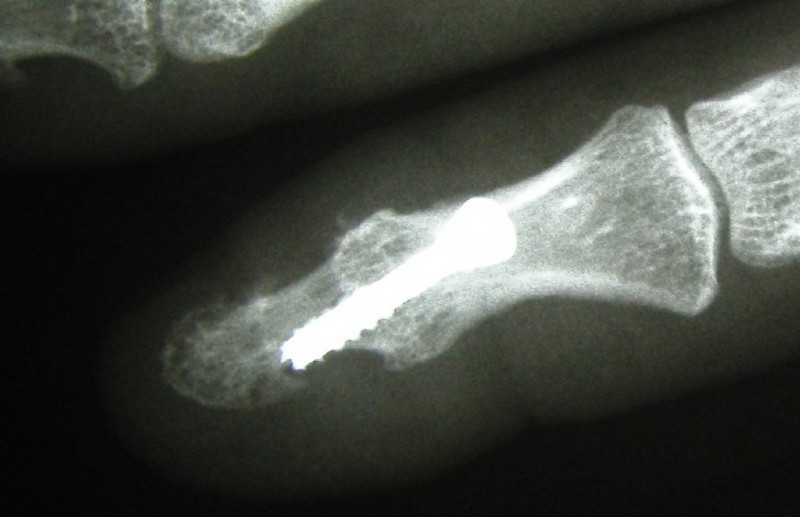

Joint replacement in the wrist area

Left: Severe osteoarthritis (abrasion, joint destruction) of the thumb-saddle joint

Middle: Replacement with a hemiarthroplasty pyrocarbon

Right: This patient had, in addition to the thumb-saddle joint osteoarthritis also signs of wear and instability between the wrist bones. She had severe pain and could not use her hand. We reinforced the pyrocarbon endoprosthesis by stiffening three wrist joints. The patient has been symptom-free for over 10 years now and can use her hand without any restrictions.